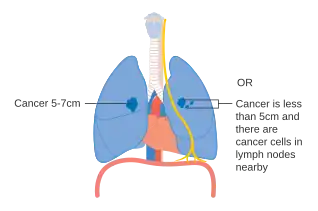

- Diagrams of main features of staging

-

Stage IA and IB lung cancer -

Stage IIA lung cancer -

Stage IIB lung cancer -

One option for stage IIB lung cancer, with T2b; but if tumor is within 2 cm of the carina, this is stage 3 -

Stage IIIA lung cancer -

Stage IIIA lung cancer, if there is one feature from the list on each side -

Stage IIIB lung cancer -

Stage IV lung cancer